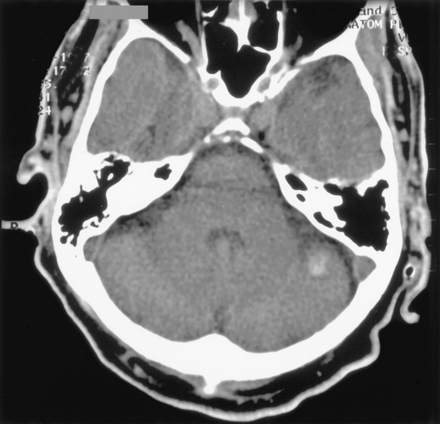

一个63岁的男人有权利M1大脑中动脉(MCA)闭塞后13天紧急冠状动脉旁路移植(CABG)对急性心肌梗死。心房扑动转换药物的前一天。他左半身不遂,视野受损的感觉在他的四肢。他最初的美国国立卫生研究院的中风尺度(署)得分是15。头部CT是正常的。被注入尿激酶200000台60分钟直接进入症状出现后血栓4小时。有良好的近端血管再通残余填充缺陷在某些M3分支(图1)。尽管国际标准化比率(INR) 1.4当天早些时候,重复INR立即过程是4.8之前完成。他得到10毫克维生素k IV肝素溶栓后开始2天。他开始他的左后立即手术。他只有一个提示视觉忽视在6周,是神经正常的病人在8个月。

一个76岁的老人有着悠久历史的冠状动脉疾病有M1 MCA闭塞冠脉搭桥术后2天。头部CT显示,没有证据表明急性缺血性梗塞或出血。他最初署得分19岁与全球失语症和右半身不遂。四个小时从症状出现,tPA 25 mg注入超过90分钟到血栓恢复只有最小流。头部CT做1天0.5 cc溶栓后显示无症状左小脑出血(图2)。静脉注射肝素溶栓后开始3天。他没有收到任何输血,尽管他在5天内从38比容下降到20%。署的分数在7天内提高11。出院时11 postprocedure天,他能够遵循简单指令但说只有单音节的词。右侧力量改善了4级(0到5医学研究委员会规模)在手臂和4.5的腿。在5个月他继续有一个明显的迟滞型失语症但能够独立执行最活动的日常生活。